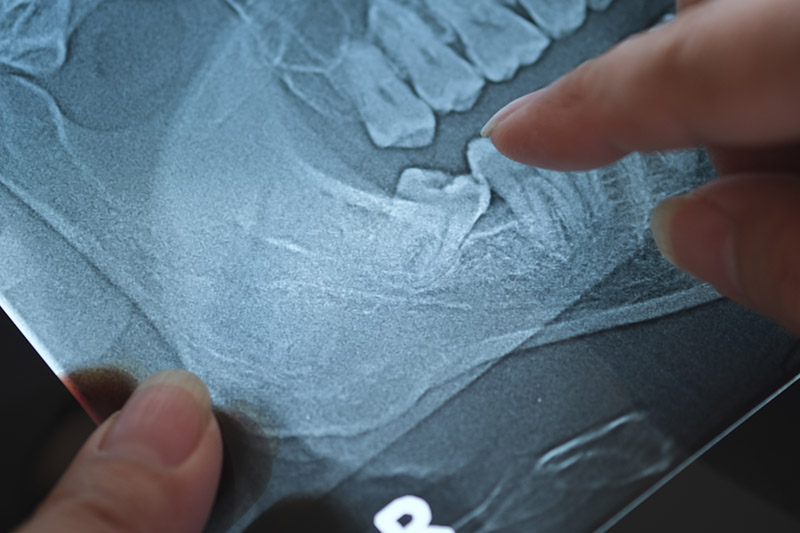

Wisdom teeth are the last set of molars to develop, typically appearing in the late teens or early twenties. At Merced Family Dental Care, we offer wisdom tooth evaluations and removal when needed to help protect your long-term oral health and comfort.

We assess each case with digital imaging and a personalized approach, so you’ll know exactly what to expect.